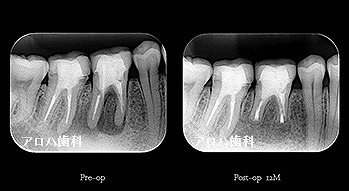

case5

左>頬側よりGP挿入。MB根尖の透過像と一致。P根にも透過像。穿孔を疑う。右>術後1年

左>術前

右>術後1年。

頬側の瘻孔